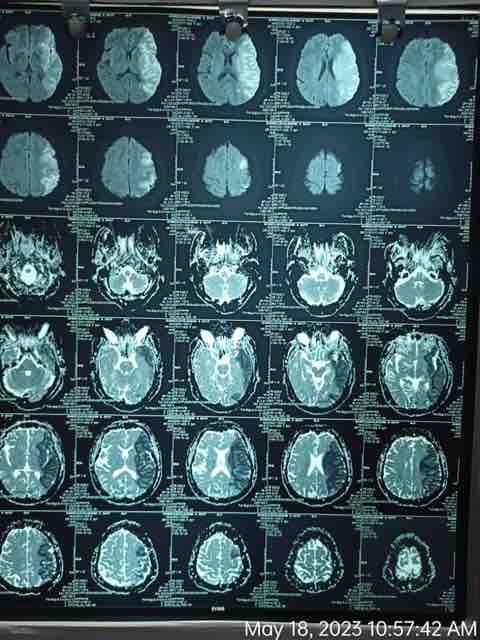

We are reaching out to you today with a heavy heart and a plea for help. Our beloved 66-year-old mother K VIJYA LAKSHMI, has been facing an incredibly challenging journey since 16th May when she had brain stroke & underwent emergency brain and abdomen surgery. Her recovery has been a rollercoaster of ups and downs.

During her hospitalization, she endured multiple complications, including respiratory distress, recurrent severe infections, and even seizure-like activity. Through it all, she has shown immense strength and determination. Still she require three more surgeries to stand on the path of recovery.